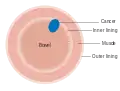

Dukes stage A bowel cancer; the cancer is only in the inner lining of the bowel.

Dukes stage A bowel cancer; the cancer is only in the inner lining of the bowel. Dukes stage B bowel cancer; the cancer has invaded the muscle.